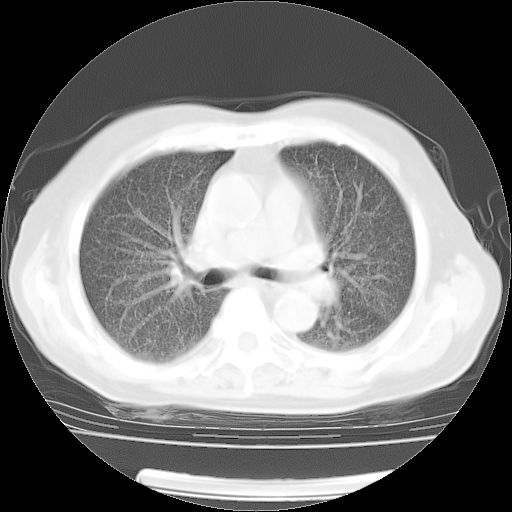

4月14日肺部CT